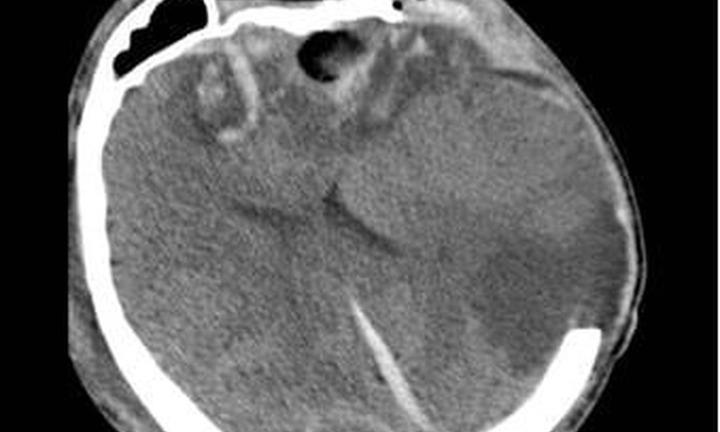

Mang thai ở tuần 26 không may gặp tai nạn giao thông, khiến sản phụ chấn thương sọ não nghiêm trọng. May mắn sau 70 ngày chiến đấu hai mẹ con đã vượt cửa tử.

Nạn nhân hôn mê khi nhập viện, chỉ số sinh hiệu ổn định. Chẩn đoán sơ bộ cho thấy chấn thương sọ não nặng do tai nạn.